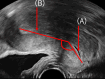

Studies have focused on uterine peristalsis and endometrial development, whereas knowledge is limited on cyclical changes in the uterocervical angle (the angle formed between the uterine corpus and cervix) during the menstrual cycle. Here, these dynamic changes were investigated. We conducted a retrospective analysis of 99 freeze-thawed blastocyst transfer cycles in 2020 and a prospective analysis of 192 cycles between 2022 and 2023. Transvaginal ultrasonography was performed to measure the uterine angle during the menstrual, ovulatory, and implantation periods. In the prospective study, conditions were standardized by instructing patients to empty their bladders and avoid uterine compression during scanning. In the retrospective analysis, the uterine angle significantly differed between the menstrual and ovulatory periods (141.1 ± 33.5° vs. 147.7 ± 40.9°, p = 0.04), but no correlation with serum estradiol or progesterone levels was observed. The prospective analysis confirmed significant differences in uterine angle between the menstrual and ovulatory periods and between the ovulatory and implantation periods (135.1 ± 27.7°, 141.5 ± 30.9°, and 136.8 ± 28.7°, respectively; both p < 0.01), without hormonal correlation. These findings suggest that the uterine angle varies throughout the menstrual cycle, becoming more anteverted during the menstrual and implantation periods and straightening around ovulation.